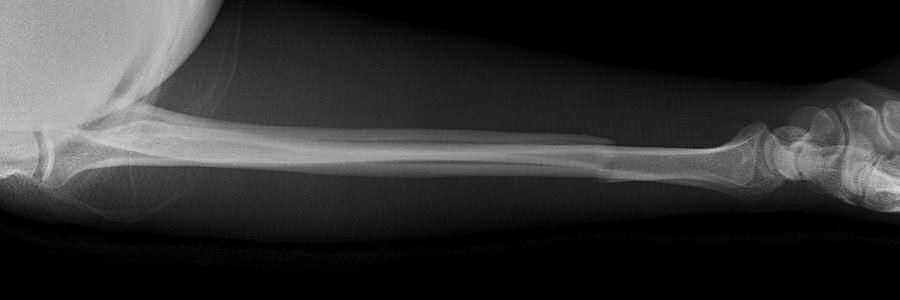

Isolerad diafysär ulnafraktur

Fraktur tvärfraktur distala tredjedelen med < 50 % felställning och < 10° vinkelfelställning (nightstick fracture)

Kalkgips (plastgips glider för lätt ner) eller ortos på underarm med fri armbåge och fri handled. Återbesök med röntgenkontroll efter 1 och 8 veckor, avgipsning efter 2 veckor (!) och därefter rörelseträning till smärtgräns. [4, 5]

Nightstickfraktur